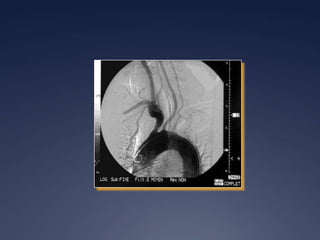

Artérite de Takayasu

 Épidémiologie

 « Maladie de la femme sans pouls »

 Prévalence plus élevée

 Japon, Asie du Sud-Est, Mexique, Amérique Latine et

Afrique

 80-90% jeune femme 20-30 ans

Critères ACR

 Artérite de Takayasu

 Âge au début de la maladie < 40 ans

 Claudication des extrémités

 Diminution du pouls artériel brachial

 Anisotension de 10 mmHg entre les bras

 Souffle artériel sous-clavier ou aortique

 Anomalie à l’artériographie

 > 3 sur 6 critères

 Sensibilité 90.5% et spécificité 97.8%

 Artérite inflammatoire chronique

 Atteint de façon caractéristique l’aorte

ascendante et les branches principales

 Pulmonaires

 Coronaires

 Carotides

 Sous-clavières

 Vertébrales

 Rénales

 Iliaques